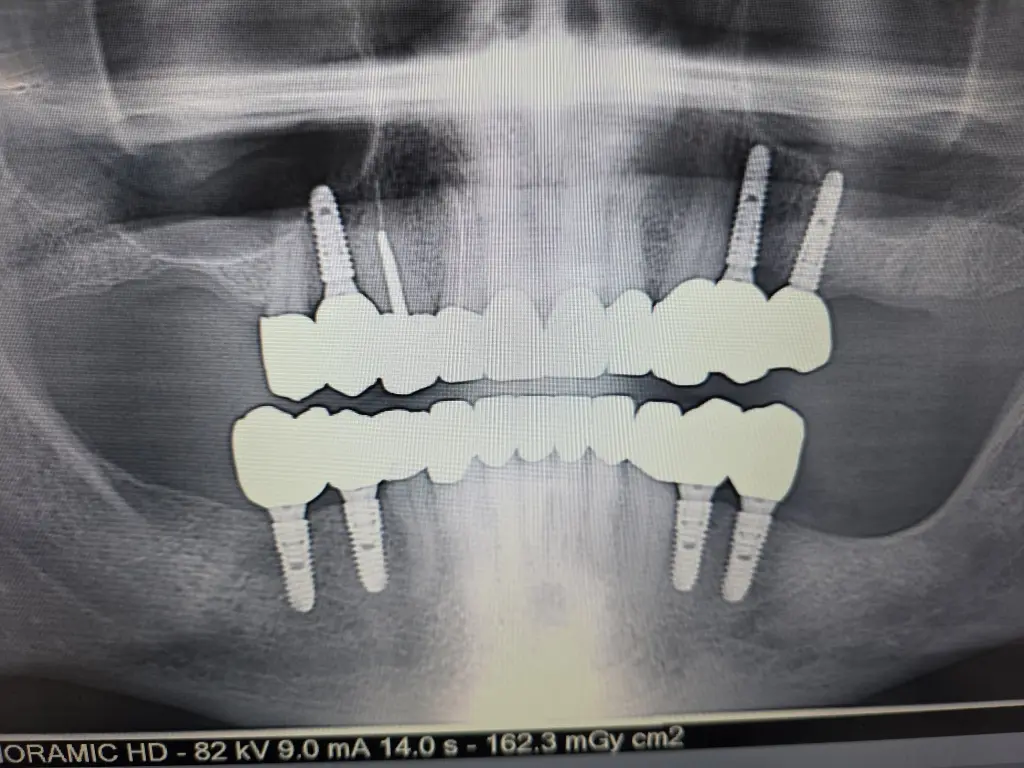

Fulll Mouth

Implants london

Full Mouth Implants

from £22,000

All Inclusive:

Surgery

Implants

IV Sedation

Zirconia Implant Bridges

5 Years Warranty